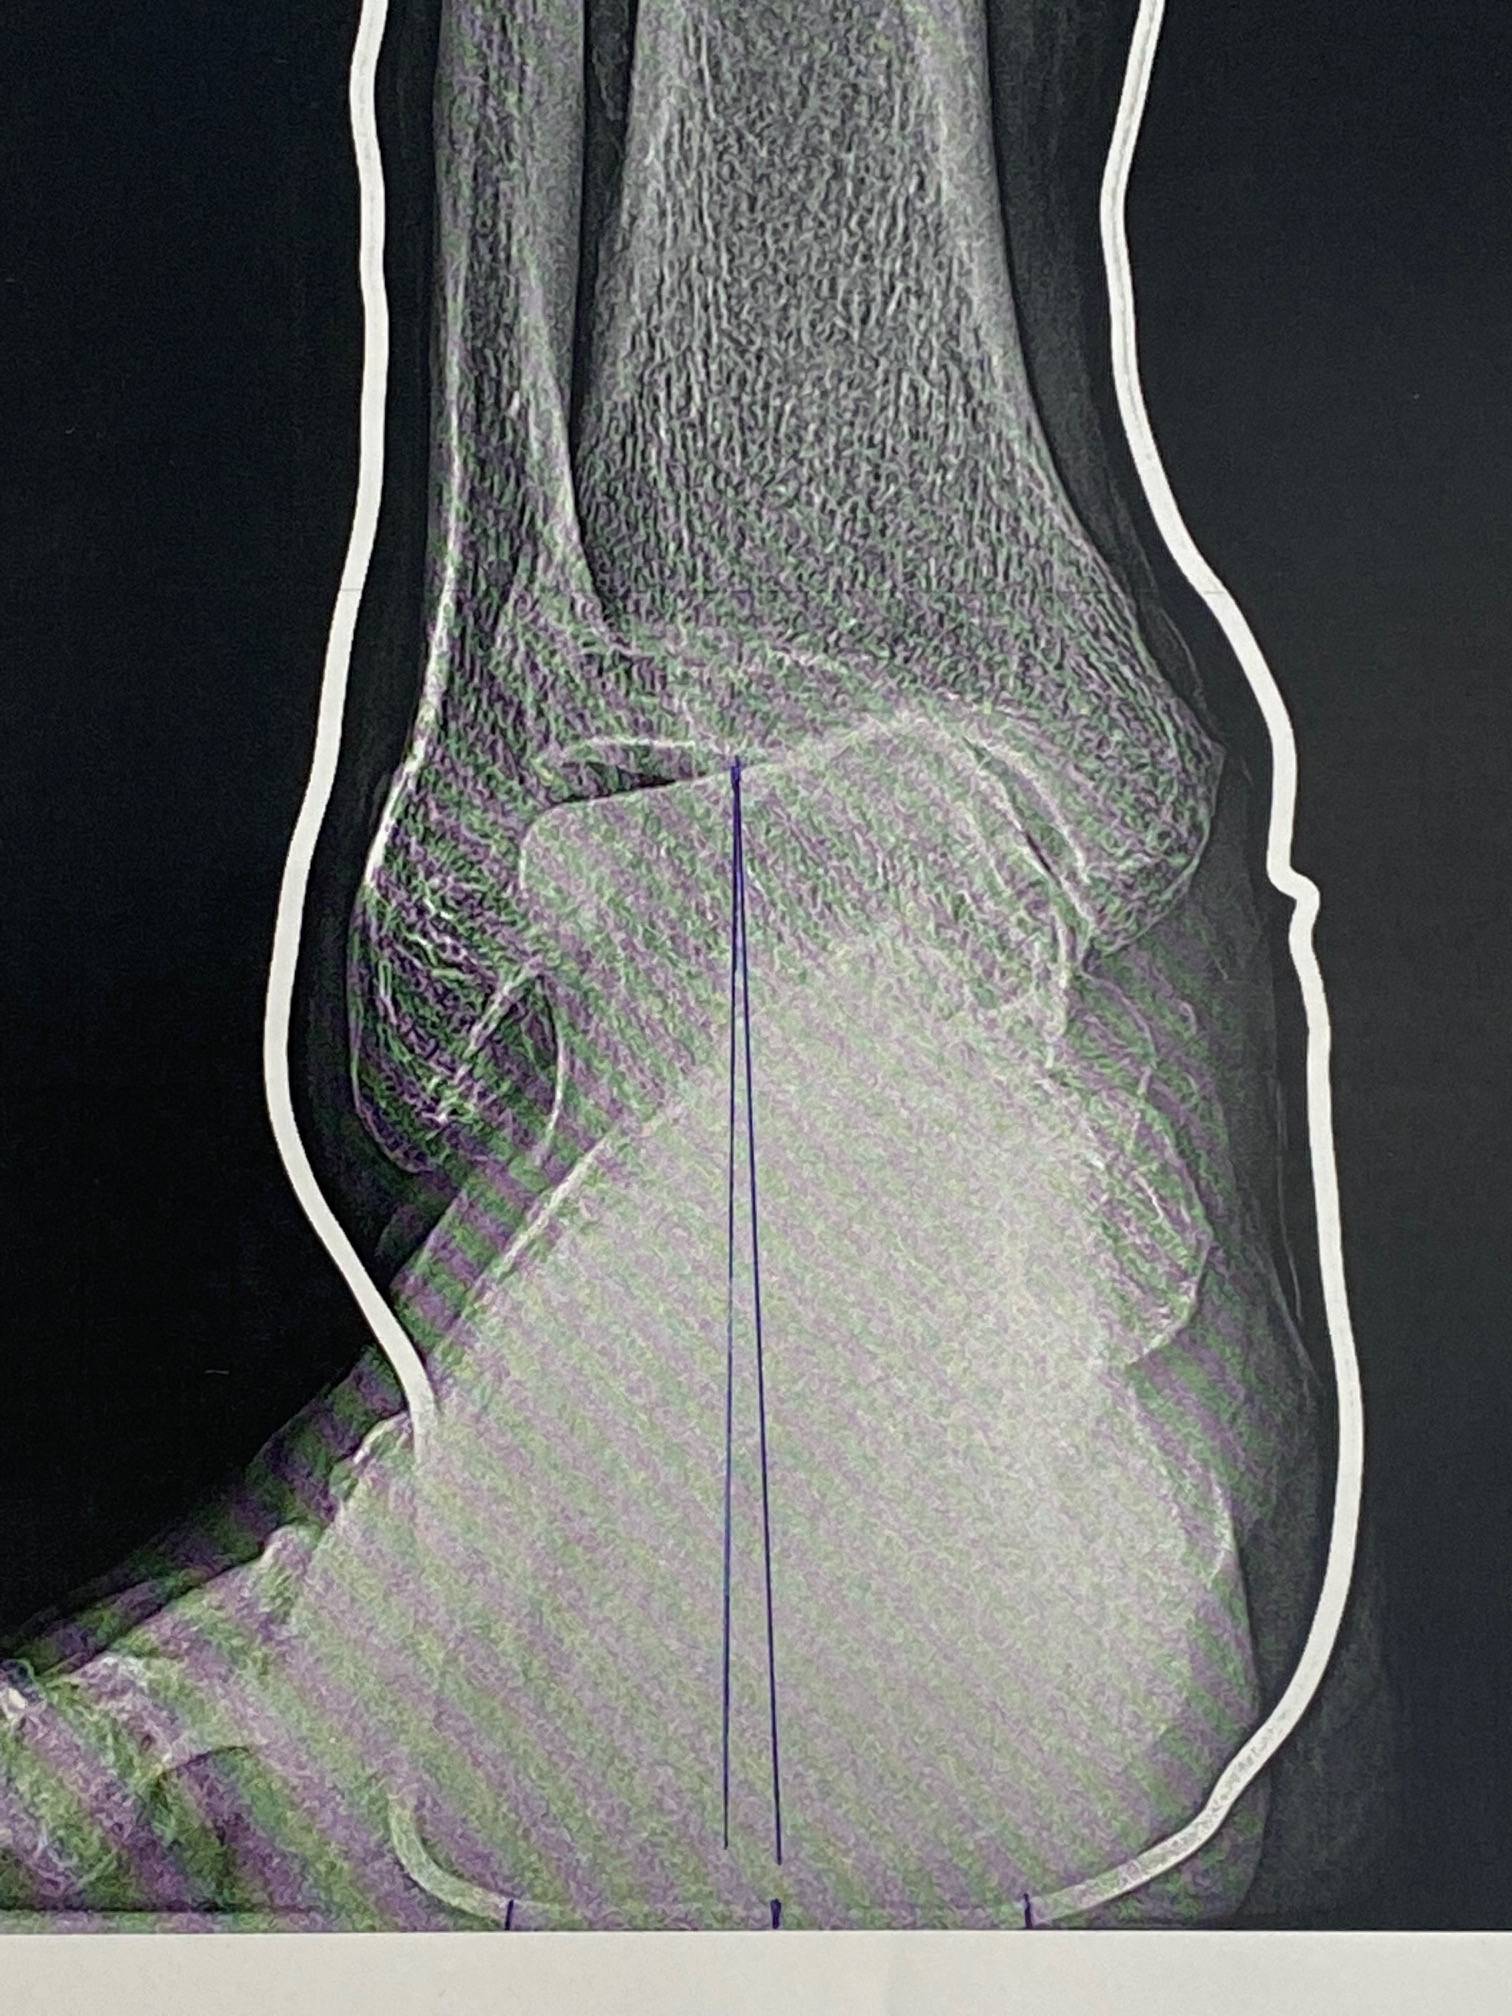

Vous trouverez, ci-dessous, quelques photos d'une ostéotomie calcanéenne de valgisation sur arthrose varisante

Institut de la Cheville et du Pied, bloc opératoire de l'ICP Paris (Clinique Blomet)